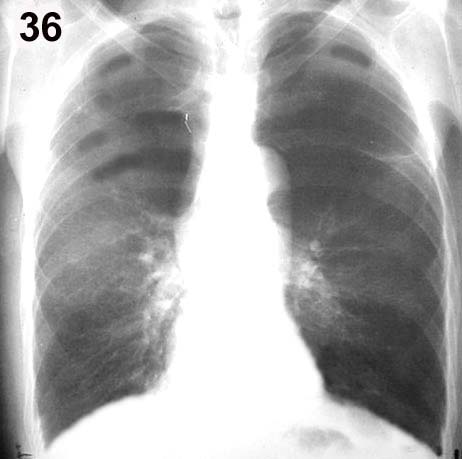

Esquema 36 Comentario placas 36 y 37 La placa corresponde a un gran fumador con enfisema pulmonar. Los lóbulos superiores y la base izquierda se ven más traslúcidos, por pobreza de vasos y los que hay son delgados y con ramificaciones escasas y distanciadas. Esta imagen es la constituye el signo radiológico específico de enfisema, que en la reproducción de la placa es poco evidente. Además los pulmones muestran signos de hiperinsuflación: aumento de volumen de los pulmones con diafragmas bajos y aplanados por debajo de la extremidad anterior de las costillas 7» u 8» y espacios intercostales dorsales horizontales y ensanchados En la placa lateral se aprecia el aplanamiento diafragmático y el aumento de contenido aéreo entre el esternón y el corazón. Si bien los signos de hiperinsuflación acompañan generalmente al enfisema no son específicos de éste y pueden observarse en otras obstrucciones bronquiales difusas como ser en el asma. Examine la placa 38 |